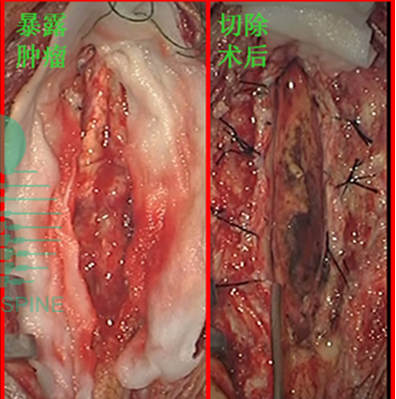

2.1 显微手术

显微手术术中CT、MRI的使用, 使术前定位更加准确,减少手术后脑脊液漏和感染的发生率并减少不必要的损伤[2]。术中电生理检测,严格将肿瘤从脊髓与其之间形成的界面分离。对肿瘤较大、分离困难者可用激光刀或超声吸引做囊内或分块切除。

3、手术过程

手术过程可能涉及术前脊髓穿刺、肿瘤栓塞,术中活检和肿瘤切除以及术中神经生理学监测。

手术,通常使用全身麻醉。

有时,在脊髓手术中,需切除一部分脊椎骨。如果是这样,就用植骨来稳定脊椎。植骨是从患者身体或已故捐赠者身上取下的骨头[2]。螺钉或金属板也可用于稳定脊柱。